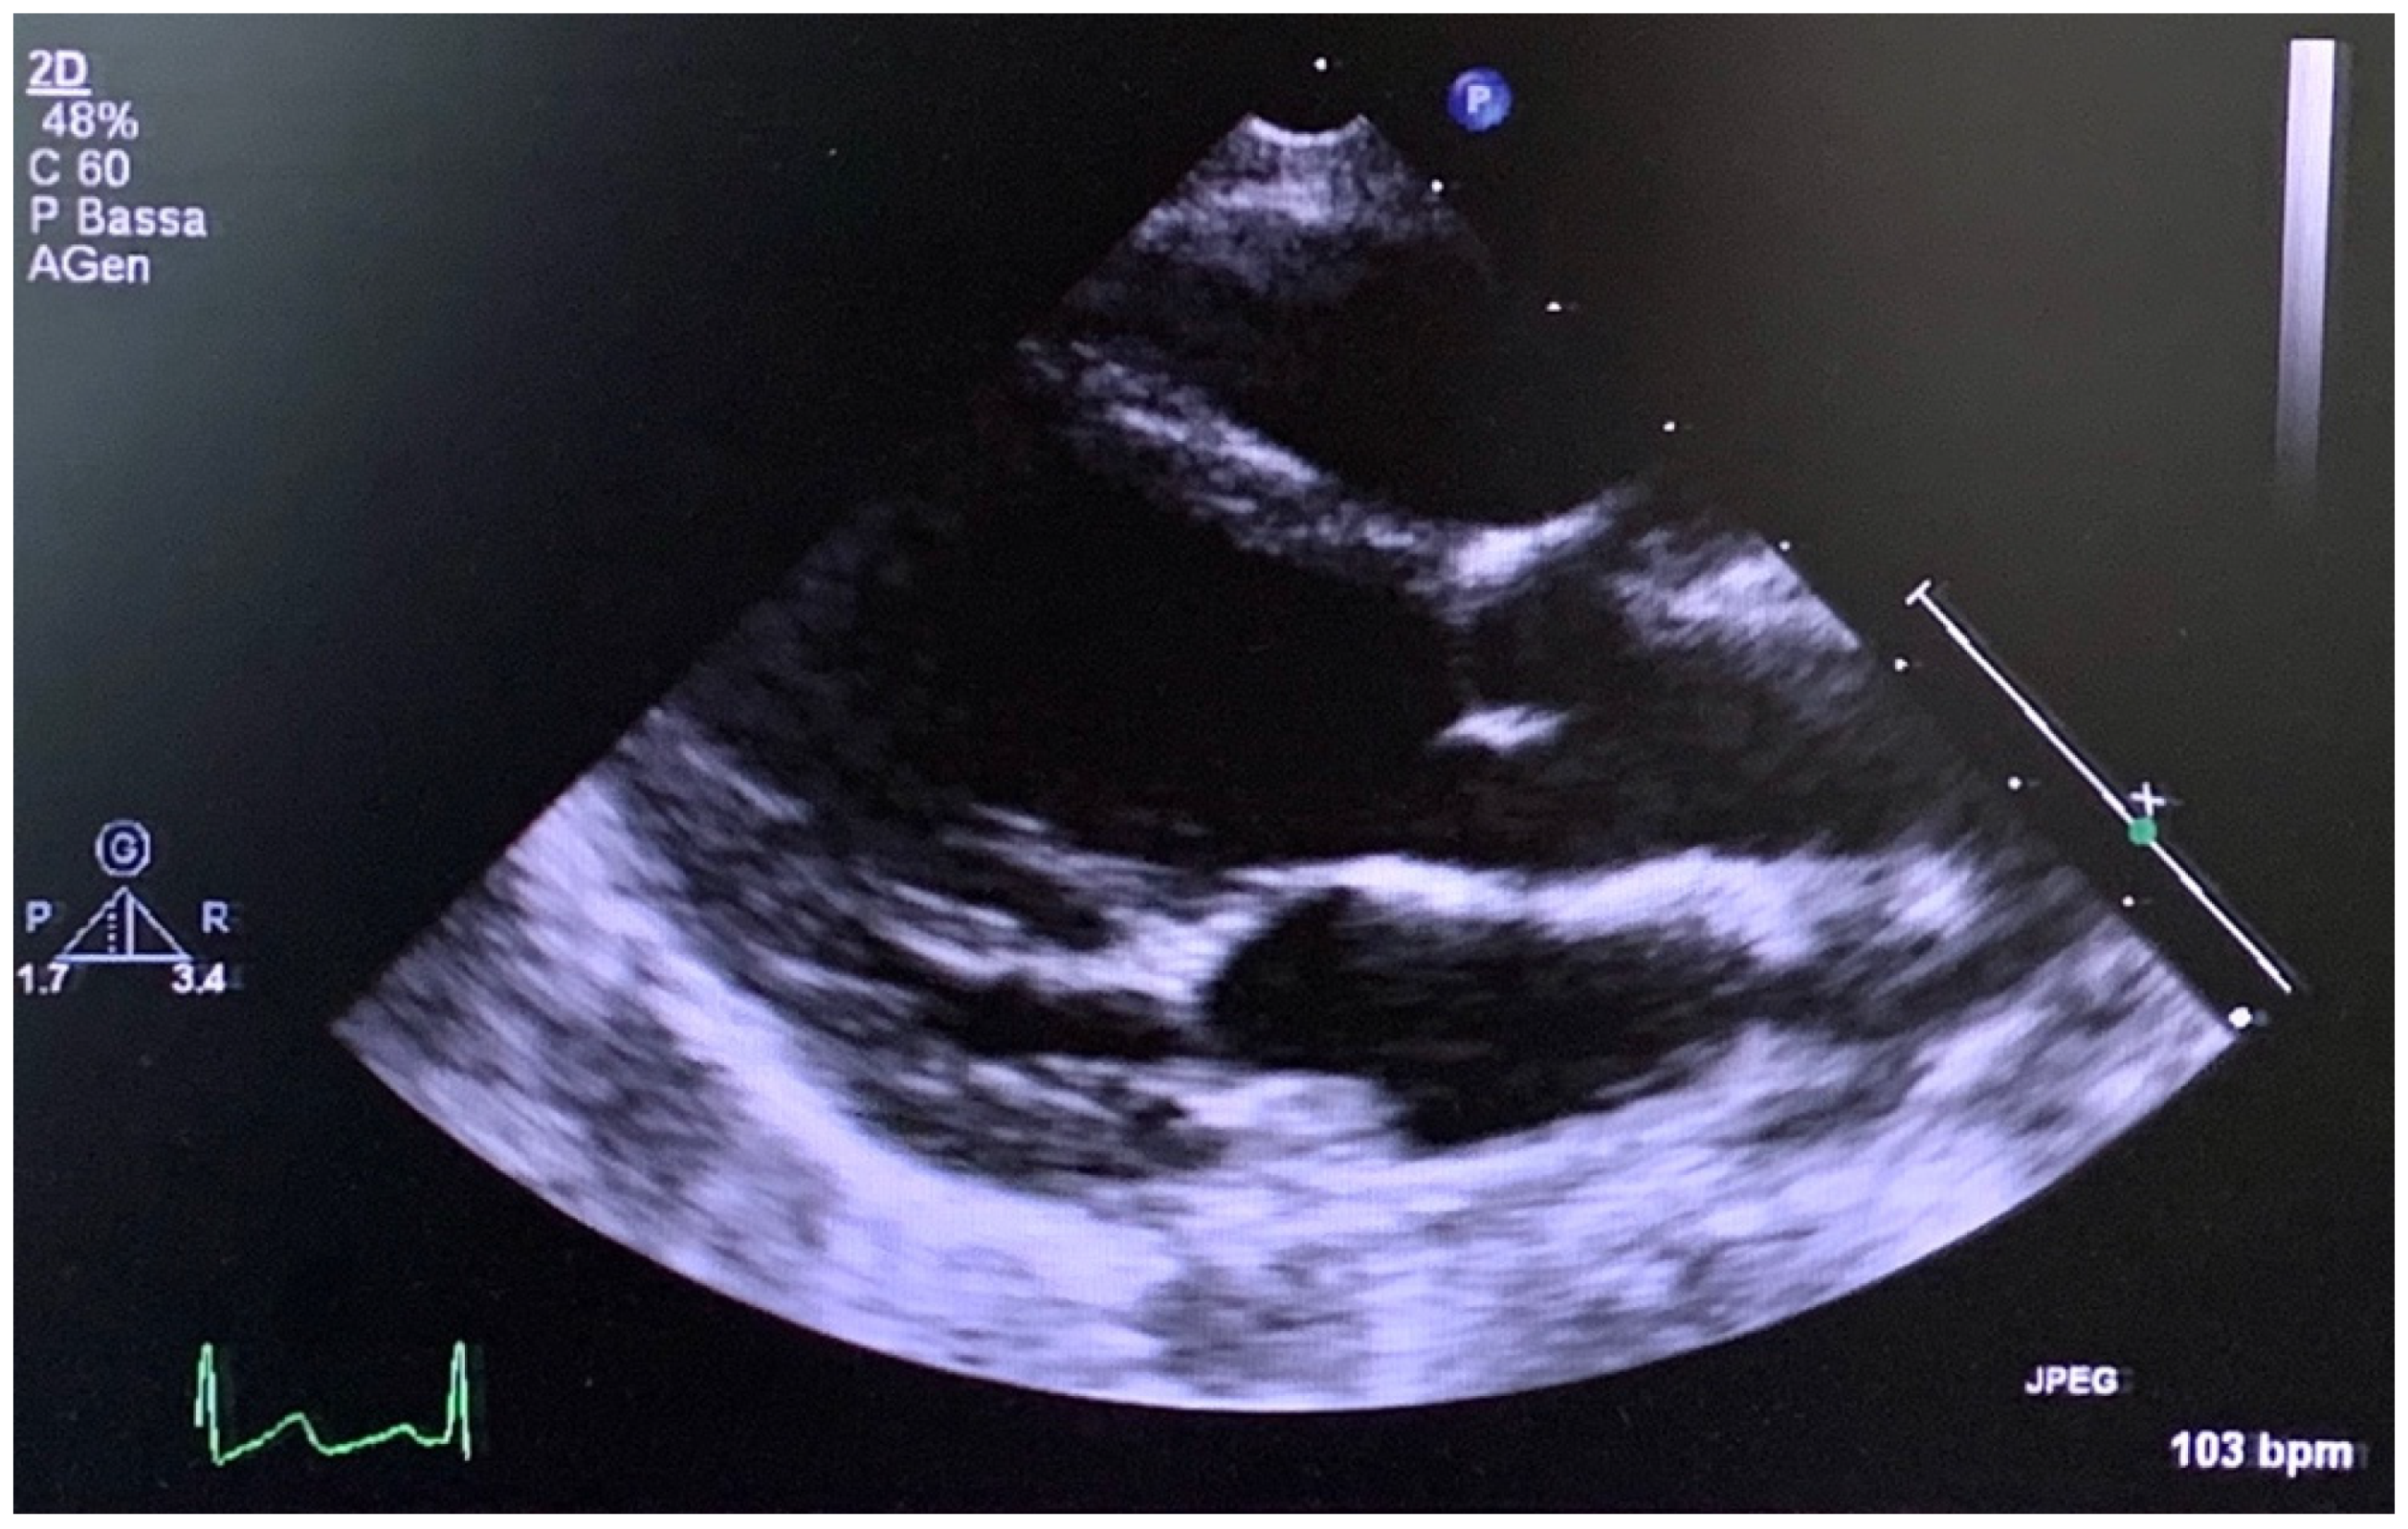

The older son of the propositus (Figure 1, III-1), assessed by the Meyer geneticists and cardiologists two years ago when he was 6 years old (Figure 4), displayed hypermobility and fetal valgus feet, which were also detected in the younger son (Figure 1, III-2) at the age of 3. The echocardiograms of both sons confirmed the absence of structural heart disease during follow-up; in particular, the image showed normal size of the aortic root (Figure 4) in the younger son (Figure 1, III-2) at 3 years old, as well as an annulus of 16 mm (z score + 1.33), Valsalva sinus of 21 mm (z score + 0.91), sino-tubular junction of 18 mm (z score + 1.31) and an ascending aorta of 17 mm (z score + 0.65). Additionally, the older son (Figure 1, III-1) presented a normal value of aortic root at 6 years old, as well as an annulus of 16 mm (z score + 0.24), Valsalva sinus of 24 mm (z score + 1.11), sino-tubular junction of 18 mm (z score − 0.96), and an ascending aorta of 17 mm (z score − 0.33).

Figure 4. At 3 years old, the echocardiogram (long axis parasternal view) of the youngest son of the propositus showed both a normal size of the aortic root and the left ventricle.